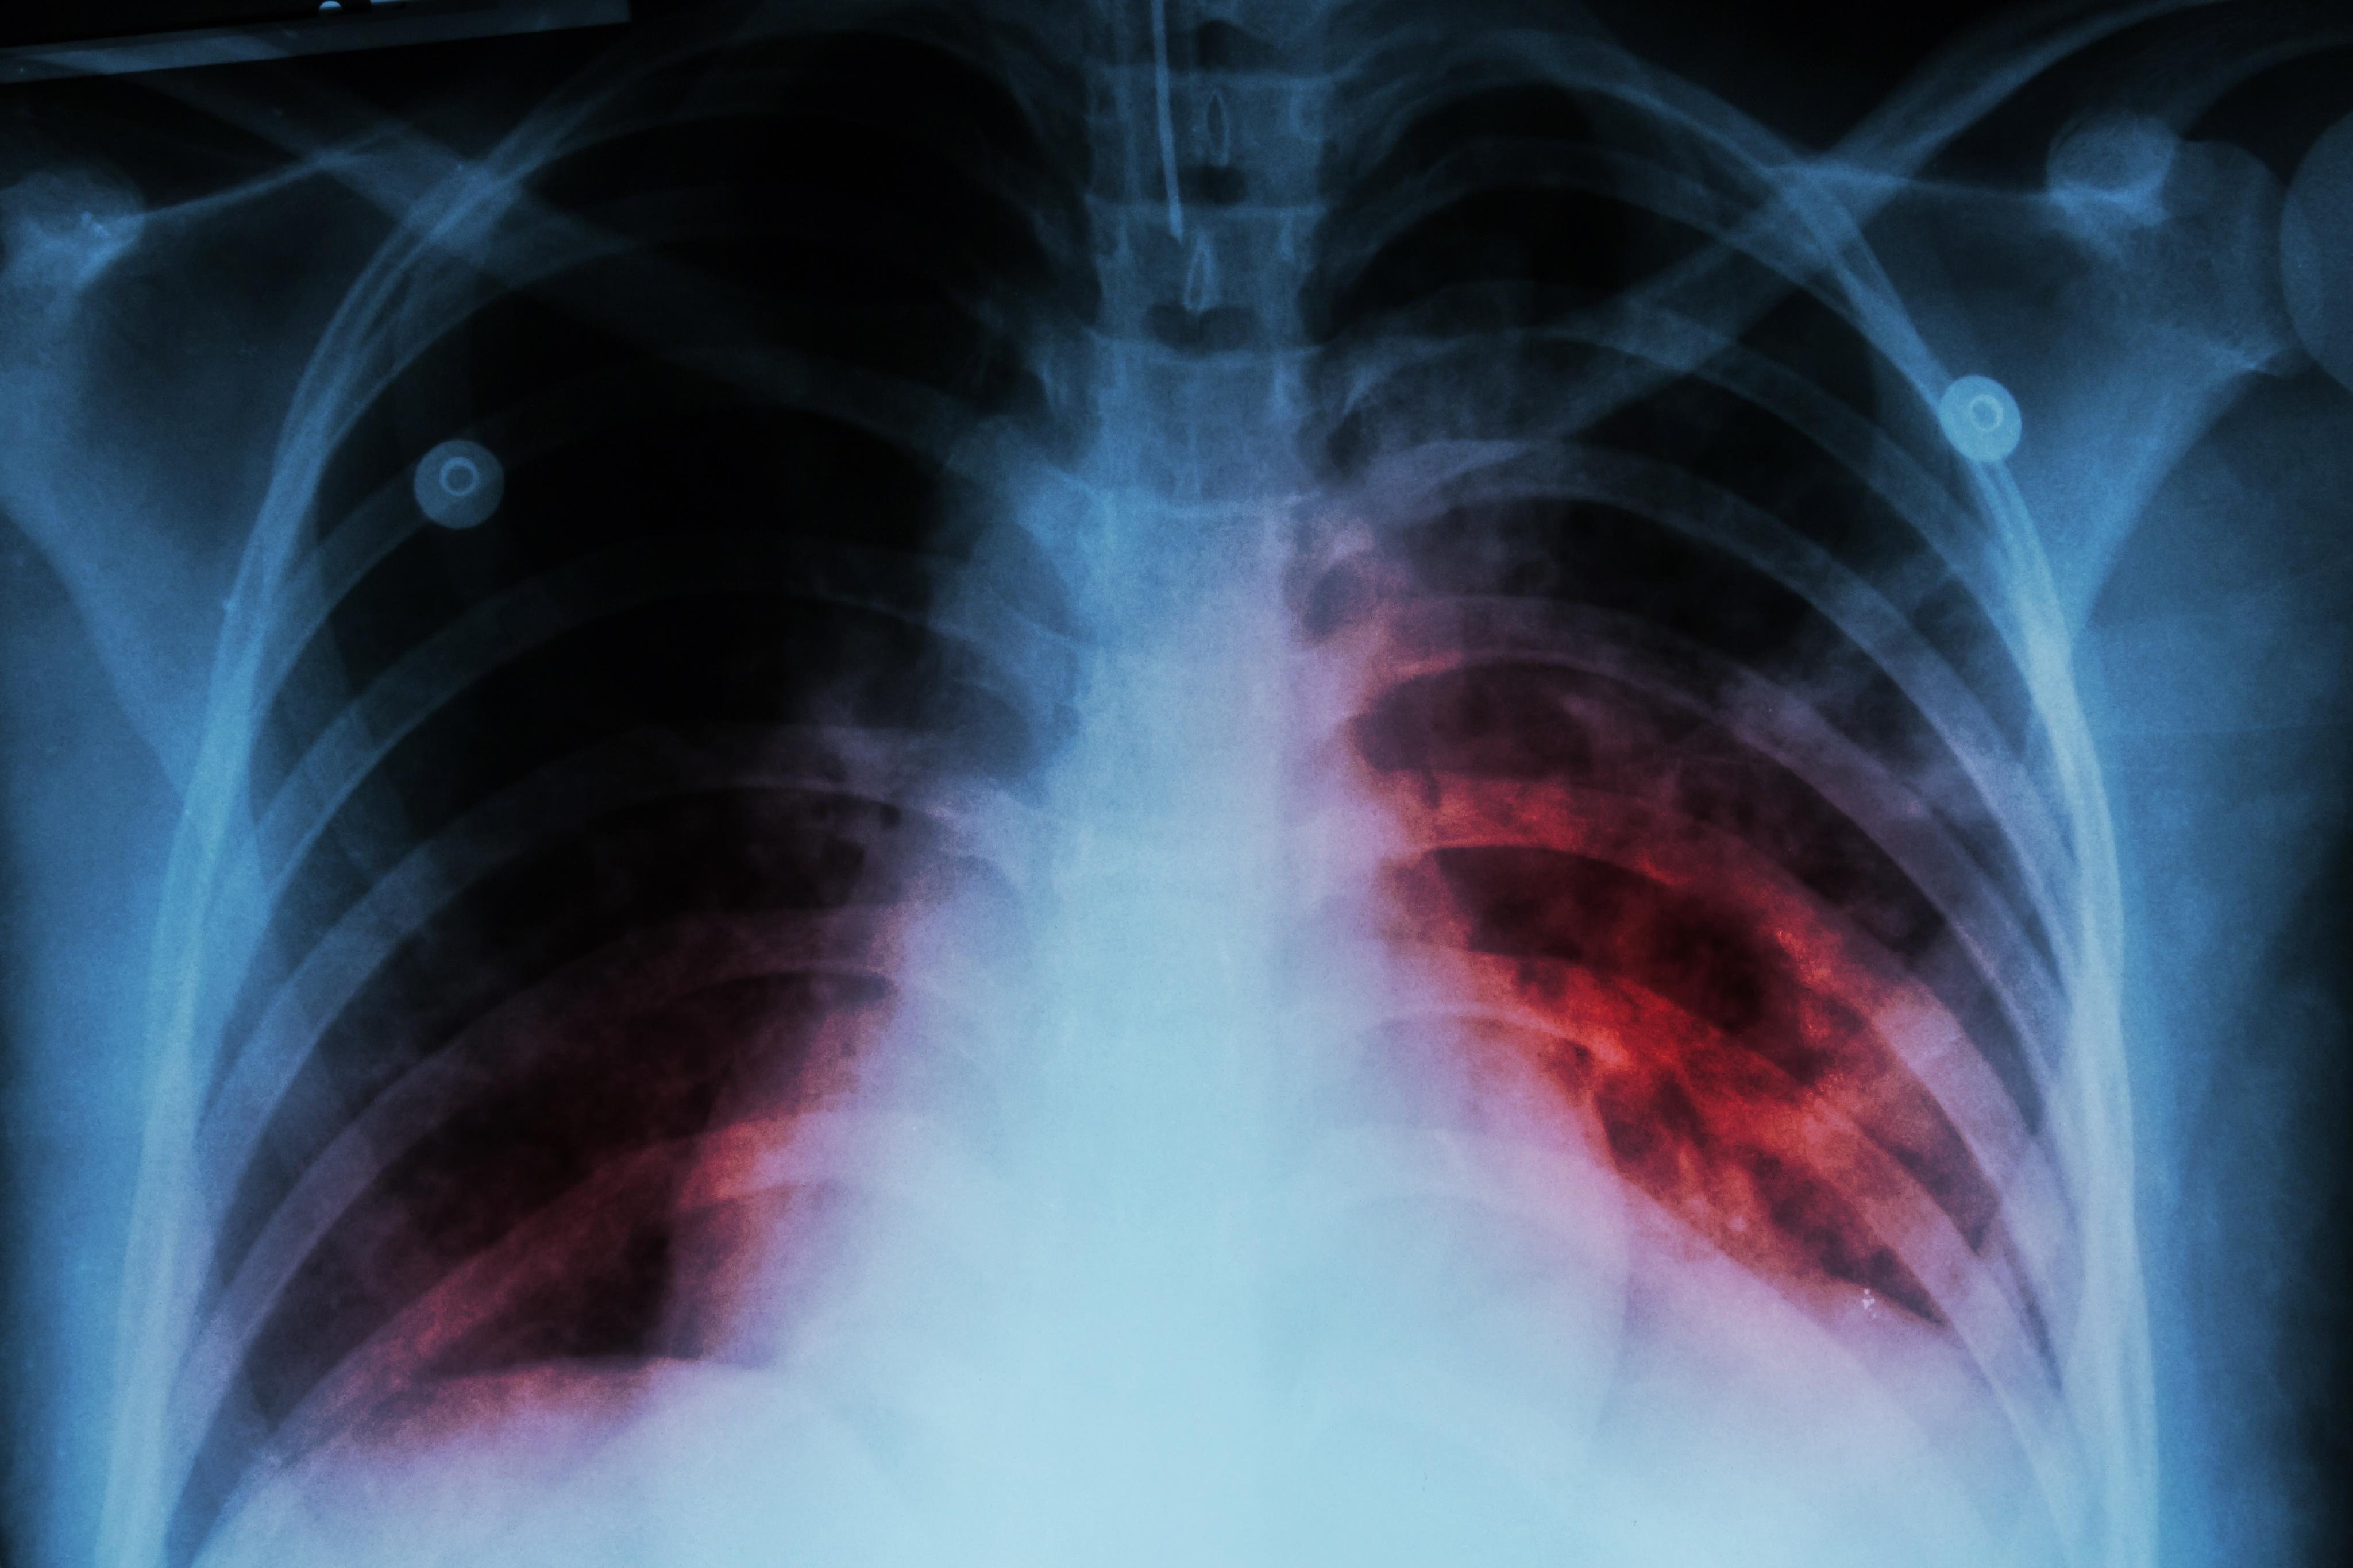

Lao là bệnh do vi khuẩn gây ra, ảnh hưởng chủ yếu đến phổi. Ảnh: iStock.